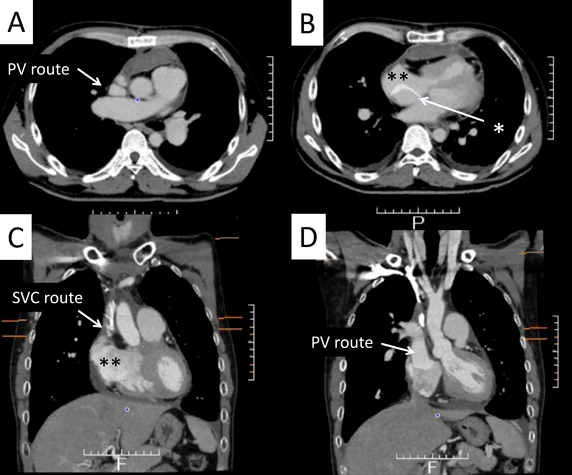

A 42-year-old man was referred to our hospital because of fatigue and exertional dyspnea; he often complained dyspnea when going up stairs. The cause of fatigue and dyspnea had not been detected, although he visited multiple clinics and his chest radiography at medical checkup already showed dilatation of the bilateral pulmonary arteries (Fig. 1A). He was unable to go to work due to his symptoms. On physical examination, his blood pressure and pulse rate were 114/86 mmHg and 78 bpm, respectively. He had a regular rhythm and a respiratory rate of 12 bpm with a percutaneous oxygen saturation of 98% in room air. His second heart sound was accentuated, and no heart murmur audible. A 6-minute walk distance was 390 m. These findings suggested that he was classified into New York Heart Association (NYHA) functional class III. Electrocardiography showed regular sinus rhythm, axis deviation and right ventricular hypertrophy with complete right bundle branch block (Fig. 1B). Echocardiography showed enlargement of the right ventricle and flattening of the interventricular septum. Doppler measurement of tricuspid regurgitation revealed that estimated right ventricular pressure was 103.1 mmHg (Fig. 2A, B). Contrast-enhanced computed tomography illustrated that the right upper and middle pulmonary veins (PVs) drained into the SVC, and that the pulmonary arteries as well as the right ventricle were dilated. Additionally, these anomalous PVs had been shifted upward due to the dilated right pulmonary artery (Fig. 3). During this investigation, the patient suddenly collapsed with low blood pressure, and immediate cardiopulmonary resuscitation was needed. Probably, PAH deteriorated subsequent to injection of contrast media, causing acute volume overload and an increase in pulmonary vascular resistance. Right heart catheterization (RHC) eventually revealed the systemic to pulmonary blood flow ratio (Qp/Qs) 1.4, mean pulmonary arterial pressure (PAP) 91 mmHg, pulmonary capillary wedge pressure 12 mmHg, and pulmonary vascular resistance (PVR) 20.3 WU, respectively (Table 1). Acute vasodilator test using the combination of inhaled oxygen and nitric oxide (iNO) showed PAP and PVR remaining unchanged. PAH related with heredity, drugs and left ventricular dysfunction, respiratory diseases were ruled out after PAH workup. Consequently, we started a combined therapy using PAH-specific drugs. Macitentan (20 mg/day) and tadalafil (10 mg/day) were immediately administered after the RHC. In addition, selexipag was gradually increased from 2 to 10 mg/day at our outpatient clinic. The second RHC took place 6 months after introduction of the PAH drugs, measuring mean PAP 49 mmHg (69/39 mmHg) and PVR 8.6 WU. The Qp/Qs ratio had increased to 2.0 (Table 1). The third RHC was carried out 9 months after initiation of the PAH drugs; mean PAP 45 mmHg (64/30 mmHg), which was similar to the value at the second RHC. Furthermore, PVR markedly improved (down to 2.7 WU), and the Qp/Qs ratio increased (up to 3.2) (Table 1). The patient’s exercise tolerance became better thereafter as his PAH improved. On the other hand, side effects of the PAH drugs, such as diarrhea and headache, gradually resulted in poor medication adherence. As interruption of PAH drugs likely results in progressive PAH, we decided to recommend surgical repair.

Fig. 3 Preoperative computed tomography

The right upper and middle pulmonary veins were connected to the superior vena cava on angiograms (A, B). Coronal and sagittal views (C, D, E) also showed right partial anomalous pulmonary venous return into the superior vena cava. White arrows: anomalous pulmonary veins, *: the superior vena cava, **: the right atrium.